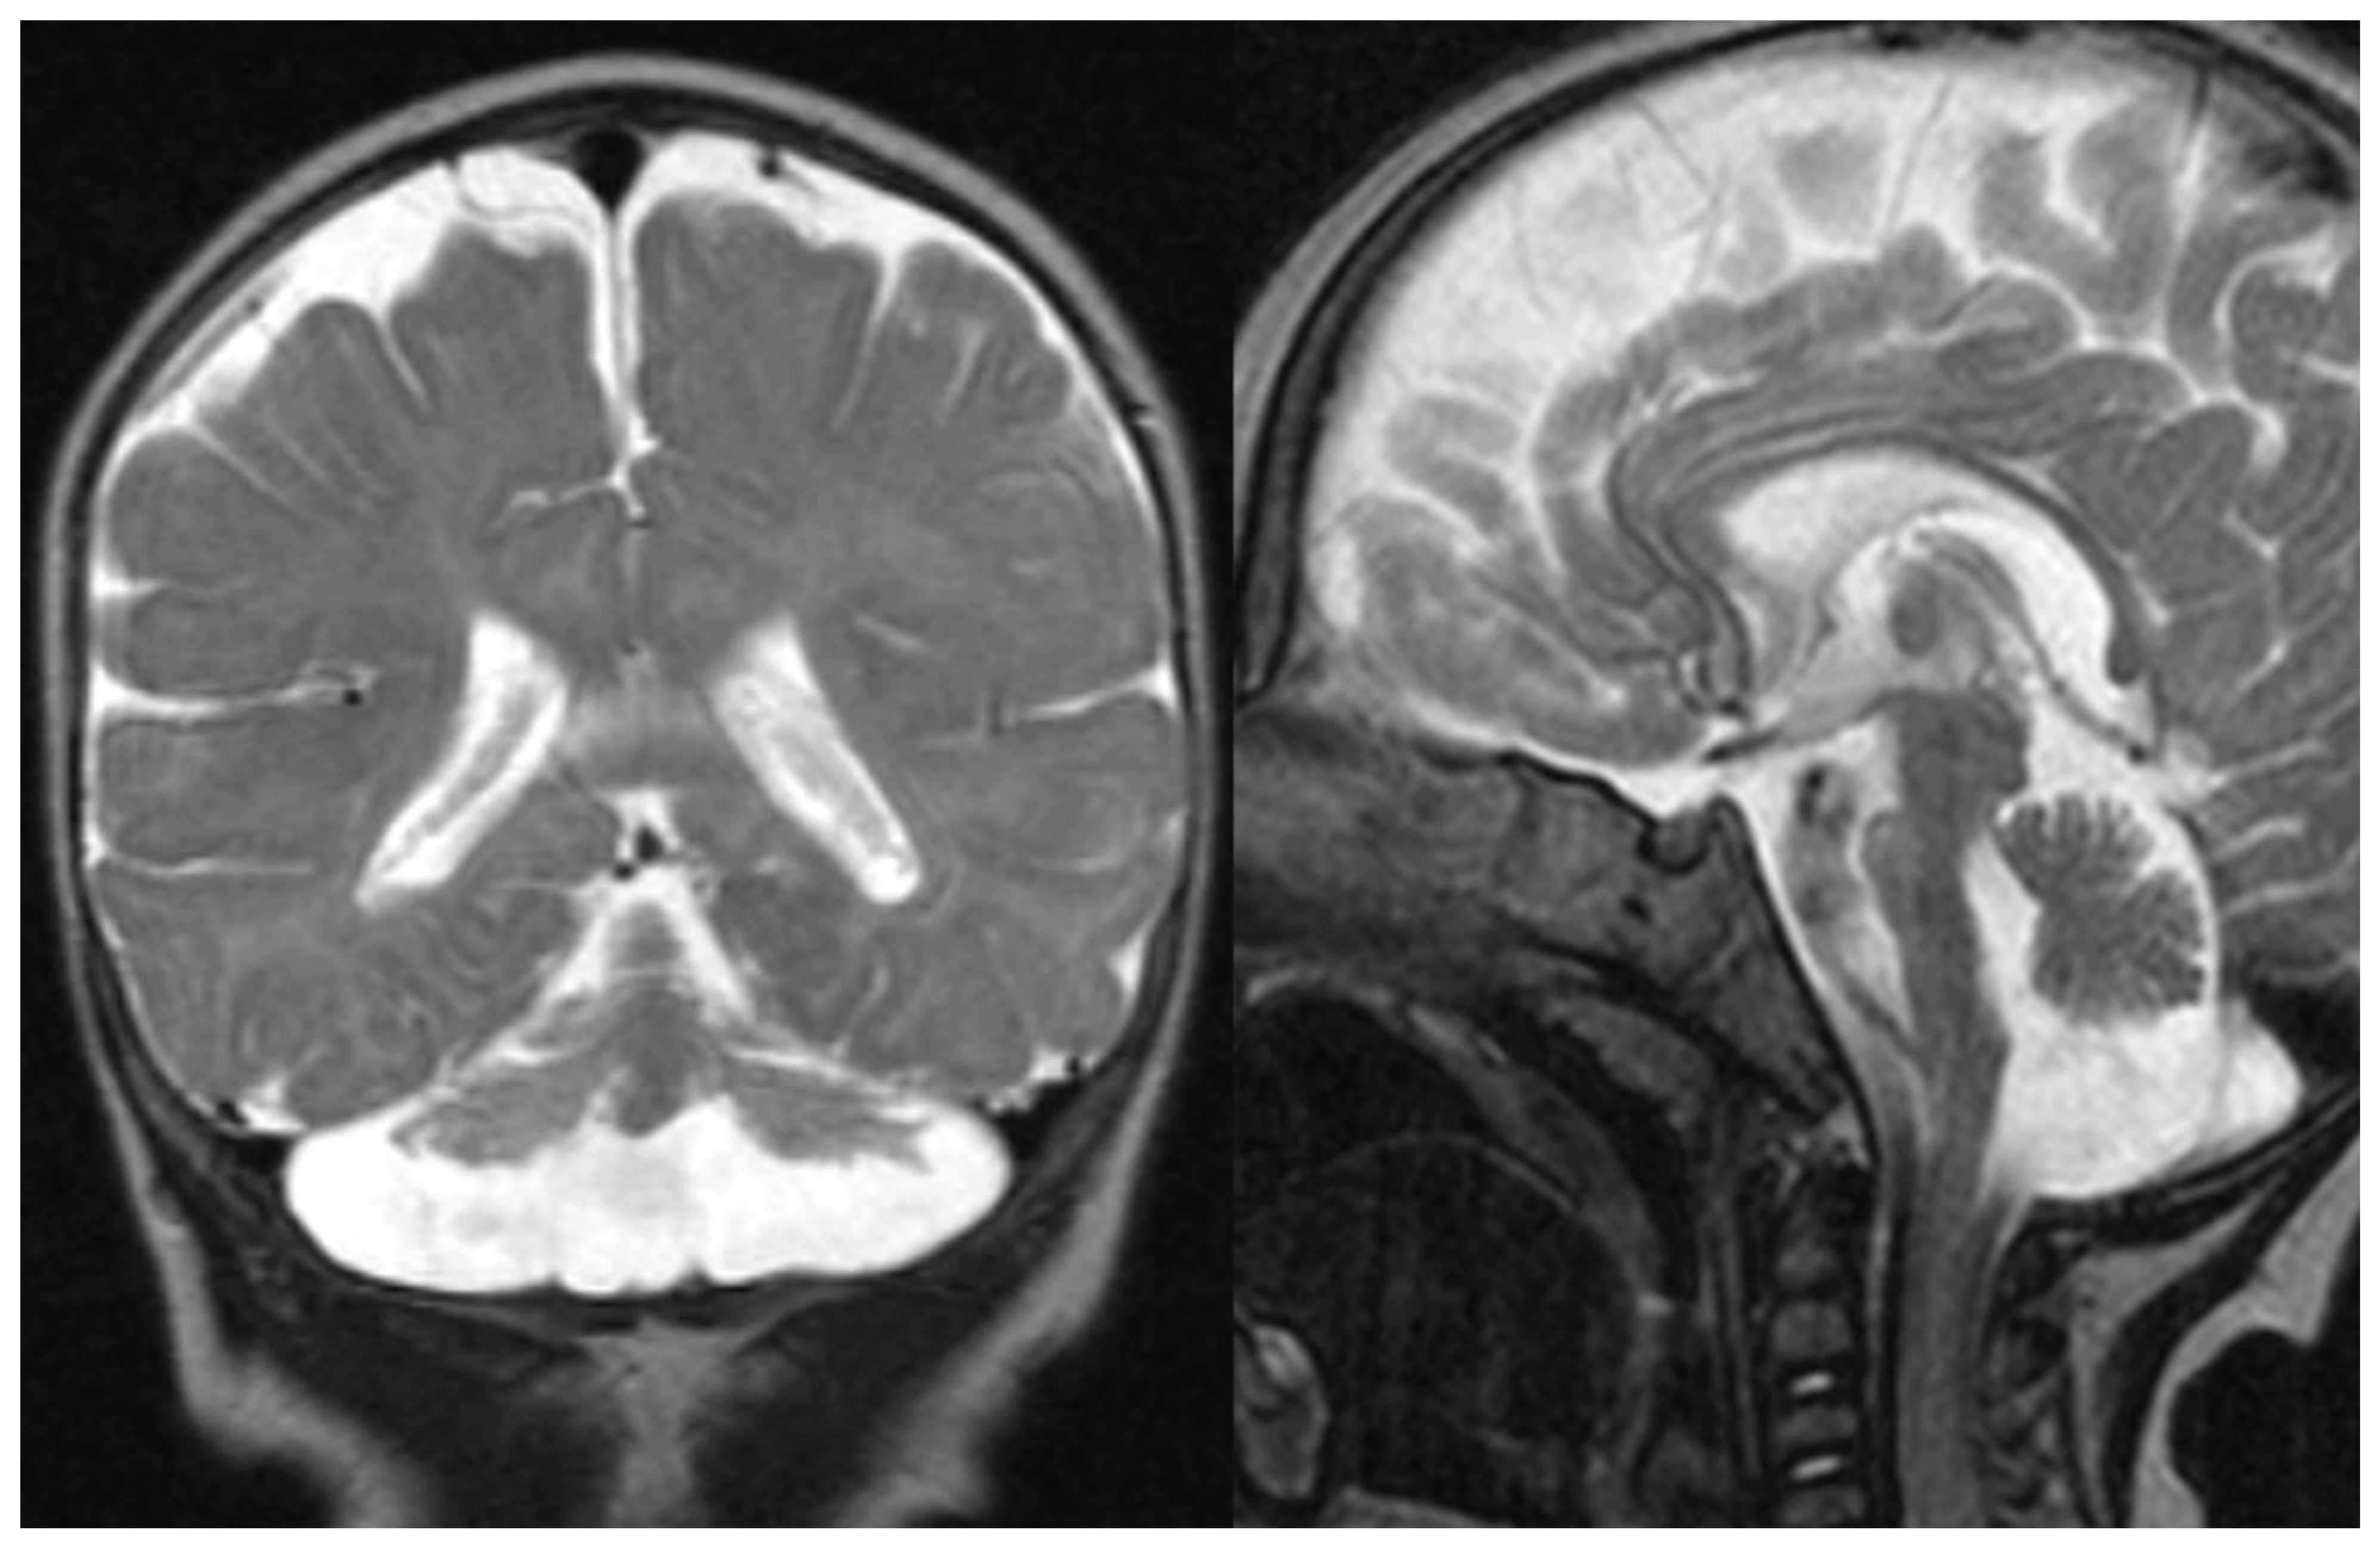

Overall, MRI in PCH patients shows a variable degree of cerebellar hypoplasia with involvement of pons and cerebrum. On coronal imaging, the particular shape of the cerebellum, named “dragonfly” or “butterfly” appearance, was described by Barth et al. [6]. The cerebellar hemispheres are particularly atrophic, with a substantial sparing of the vermis. Flattening of the caudate nuclear heads can be present [5]. Additional inconstant findings are cerebellar cysts (PCH 1, 2, and 6), agenesis of the corpus callosum (PCH 9), simplified gyral pattern (PCH 6 and 10), and hypomyelination (PCH 1, 2, 6, and 9). In several PCH, pons could be relatively preserved, and in PCH10, the cerebellum is mostly normal 11. The presence of C-shaped inferior olive has been reported in PCH2, suggesting a prenatal onset 9 (Figure 1).

Figure 1.

PCH 2. Brain MRI scan of a 1-year-old girl with TSEN 54 mutation. MR images demonstrate the characteristic “dragonfly-like” cerebellar pattern: severe hypoplasia of the cerebellar hemispheres with a relative sparing of the vermis. Note the flat ventral surface of the pons and thin corpus callosum.

Figure 2.

PCH6. Brain MRI scan of a 5-year-old boy. The size of the pons is almost normal, the vermis grossly diminished with enlarged interfolial spaces. Vermis and hemispheres are equally hypoplastic.